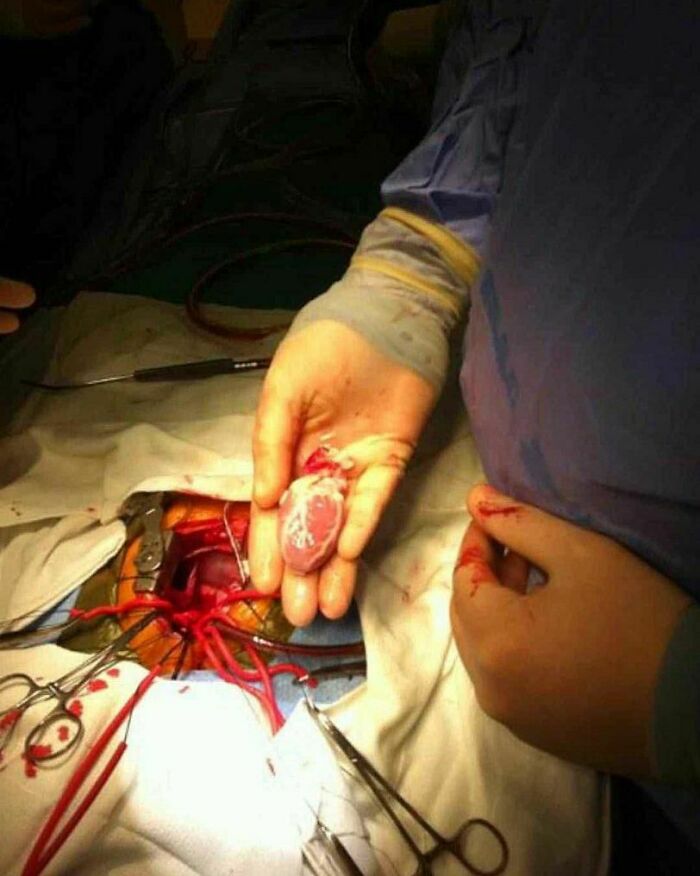

Pediatric Heart Transplant Procedure!

Heart Transplant! Bad Heart Going Out And A New Heart Going In!